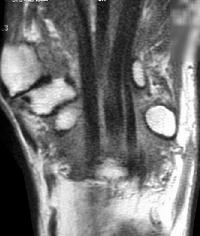

Sections through the carpal tunnel -  looking for a hook of hamate fracture or tendon discontinuity - were read as normal, although there may be a subtle signal irregularity through the hook of the hamate: